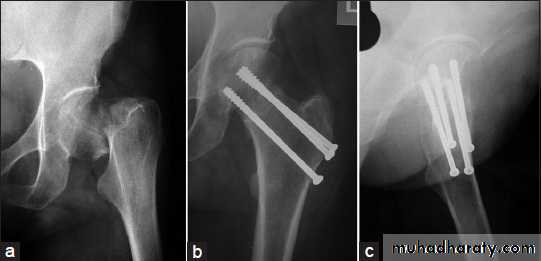

INTERNAL FIXATION

Indications

advantages